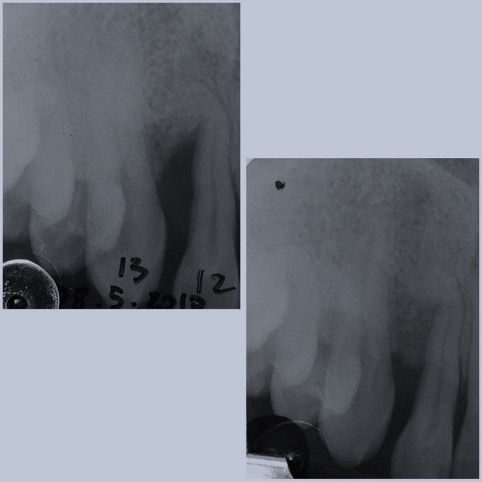

Successivamente ad una valutazione della bocca del paziente, la terapia della parodontite consisterà in:

una PRIMA FASE non chirurgica definita causale il cui scopo è quello di eliminare i processi infettivi ed infiammatori mediante un’ ablazione del tartaro superficiale con ultrasuoni ed uno scaling e root planning in cui il paziente, sotto anestesia, verrà sottoposto ad un curettage con stumenti manuali per raggiungerele zone più profonde all’interno della gengiva associando se necessaria una terapia farmacologica.

Illustrate al paziente le adeguate istruzioni di igiene orale verrà fatta una seconda rivalutazione ai 3 mesi dal trattamento.

UNA SECONDA FASE, se necessaria, chirurgica resettiva o rigenerativa con la eliminazione/ ricostruzione dei difetti ossei e gengivali provocati dall’ infezione.

La presenza di batteri infatti comporta un riassorbimento dell’osso intorno ai denti dovuto in parte ai metaboliti prodotti dai batteri stessi, in parte ai mediatori della risposta infiammatoria cronica dell’organismo.